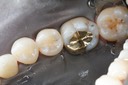

Kris Nip #19 pre-op

Kris Nip #19 amalgam removal

Kris Nip #19 caries removal

Kris Nip #19 prep

Kris Nip #19 prep lingual view

Kris Nip #19 finish